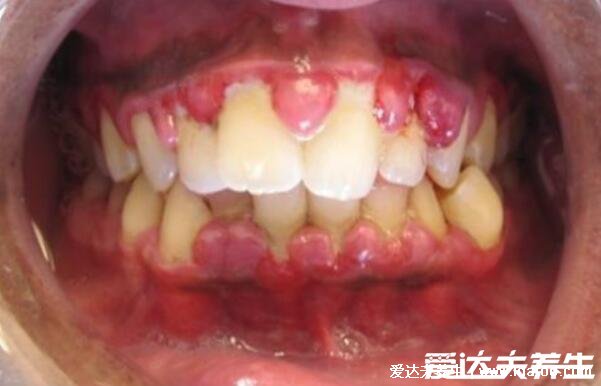

牙龈癌的早期三大症状,注意病程极长口腔溃疡/牙齿松动/张口困难

牙龈癌的早期三大症状

1、口腔溃疡

如果大家目前是有口腔溃疡的情况的话,是要引起注意的,特别是这个溃疡长时间不治愈,反复发作并且病程较长的情况,因为牙龈癌是可以让人出现反复的口腔溃疡的,而且是可以将时间持续到6个月左右的时间,这是要在注意的。大家可以注意这溃疡的边缘是会凸起的,在它的中心部是凹陷的,牙龈上出现溃疡状、结节状等的肿块。进一步发展可以出现牙齿松动。

对于牙龈癌的早期三大症状,大家是可以了解的,但是具体的诊断是由医生帮你看看,对于牙龈癌的症状,注意肿块是会有出血,以及后续等是会有局部淋巴结肿大疼痛等的。